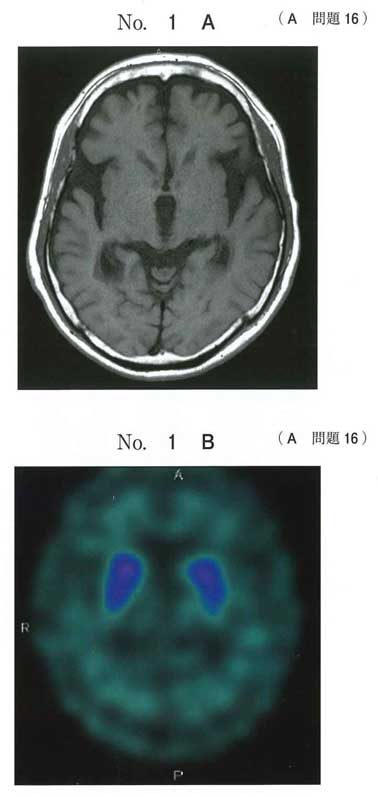

BでPSPすっすね

a Parkinson病

→ 初期は転倒少ない/L-dopa有効なことが多い ❌

b 進行性核上性麻痺

→ 垂直注視麻痺+早期転倒+L-dopa無効 ⭕️

c 筋萎縮性側索硬化症

→ 運動ニューロン徴候がない ❌

d 特発性正常圧水頭症

→ 歩行障害・認知・尿失禁、SPECT所見が合わない ❌

e 血管性Parkinson症候群

→ 画像に多発梗塞がない、眼球運動障害は非典型 ❌